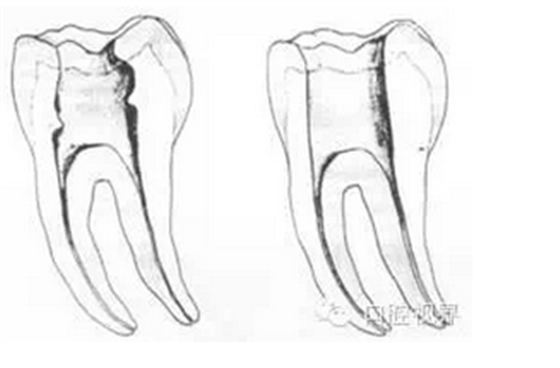

左圖為正常開髓孔的大小和位置。左邊圖為下顎,右邊圖為上顎。